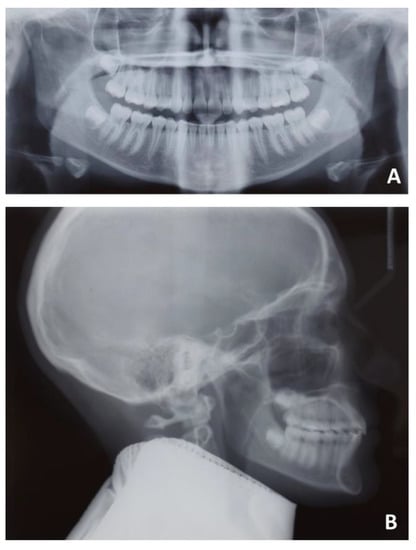

The second case was concerned with the orthodontic treatment with transparent aligners of a growing patient with dentoskeletal class II malocclusion, scissor bite of the first right upper premolar, a slight contraction of the upper and lower arches, lower dental crowding and an interincisive diastema.

The patient also had good exposure to their smile and deep bite, so it was indicated to correct the deep bite by leveling the lower arch with the intrusion of the canines and incisors (Figure 15 and Figure 16).

The patient presented a skeletal class II malocclusion, a normodivergent growth pattern, excessive proclination of the upper incisors and a normoinclination of the lower incisors (Figure 17 and Table 3).

Figure 16. Pre-treatment radiographic of case number 2: (A) orthopantomography; (B) lateral cephalogram.